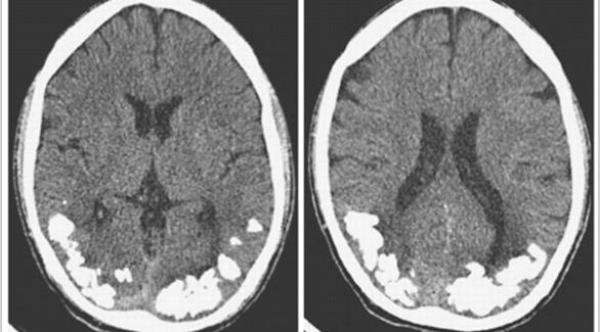

وكان يعتقد أنه مصاب بالصداع النصفي، ويتناول مسكنات الصداع دون أن تظهر أي علامات على التحسن، لكن صورة الأشعة أظهرت تراكم حجارة صغيرة من الكلس في الجزء الخلفي من دماغه، وهي المنطقة المسؤولة عن الرؤية.

ويقول الأطباء في جامعة ساو باولو، إنه ليس من الواضح بعد كيف تسبب مرض الاضطرابات الهضمية في تراكم الحجارة الكلسية في الدماغ، لكنهم أشاروا إلى أن عدم القدرة على امتصاص الحديد ربما يكون هو السبب.